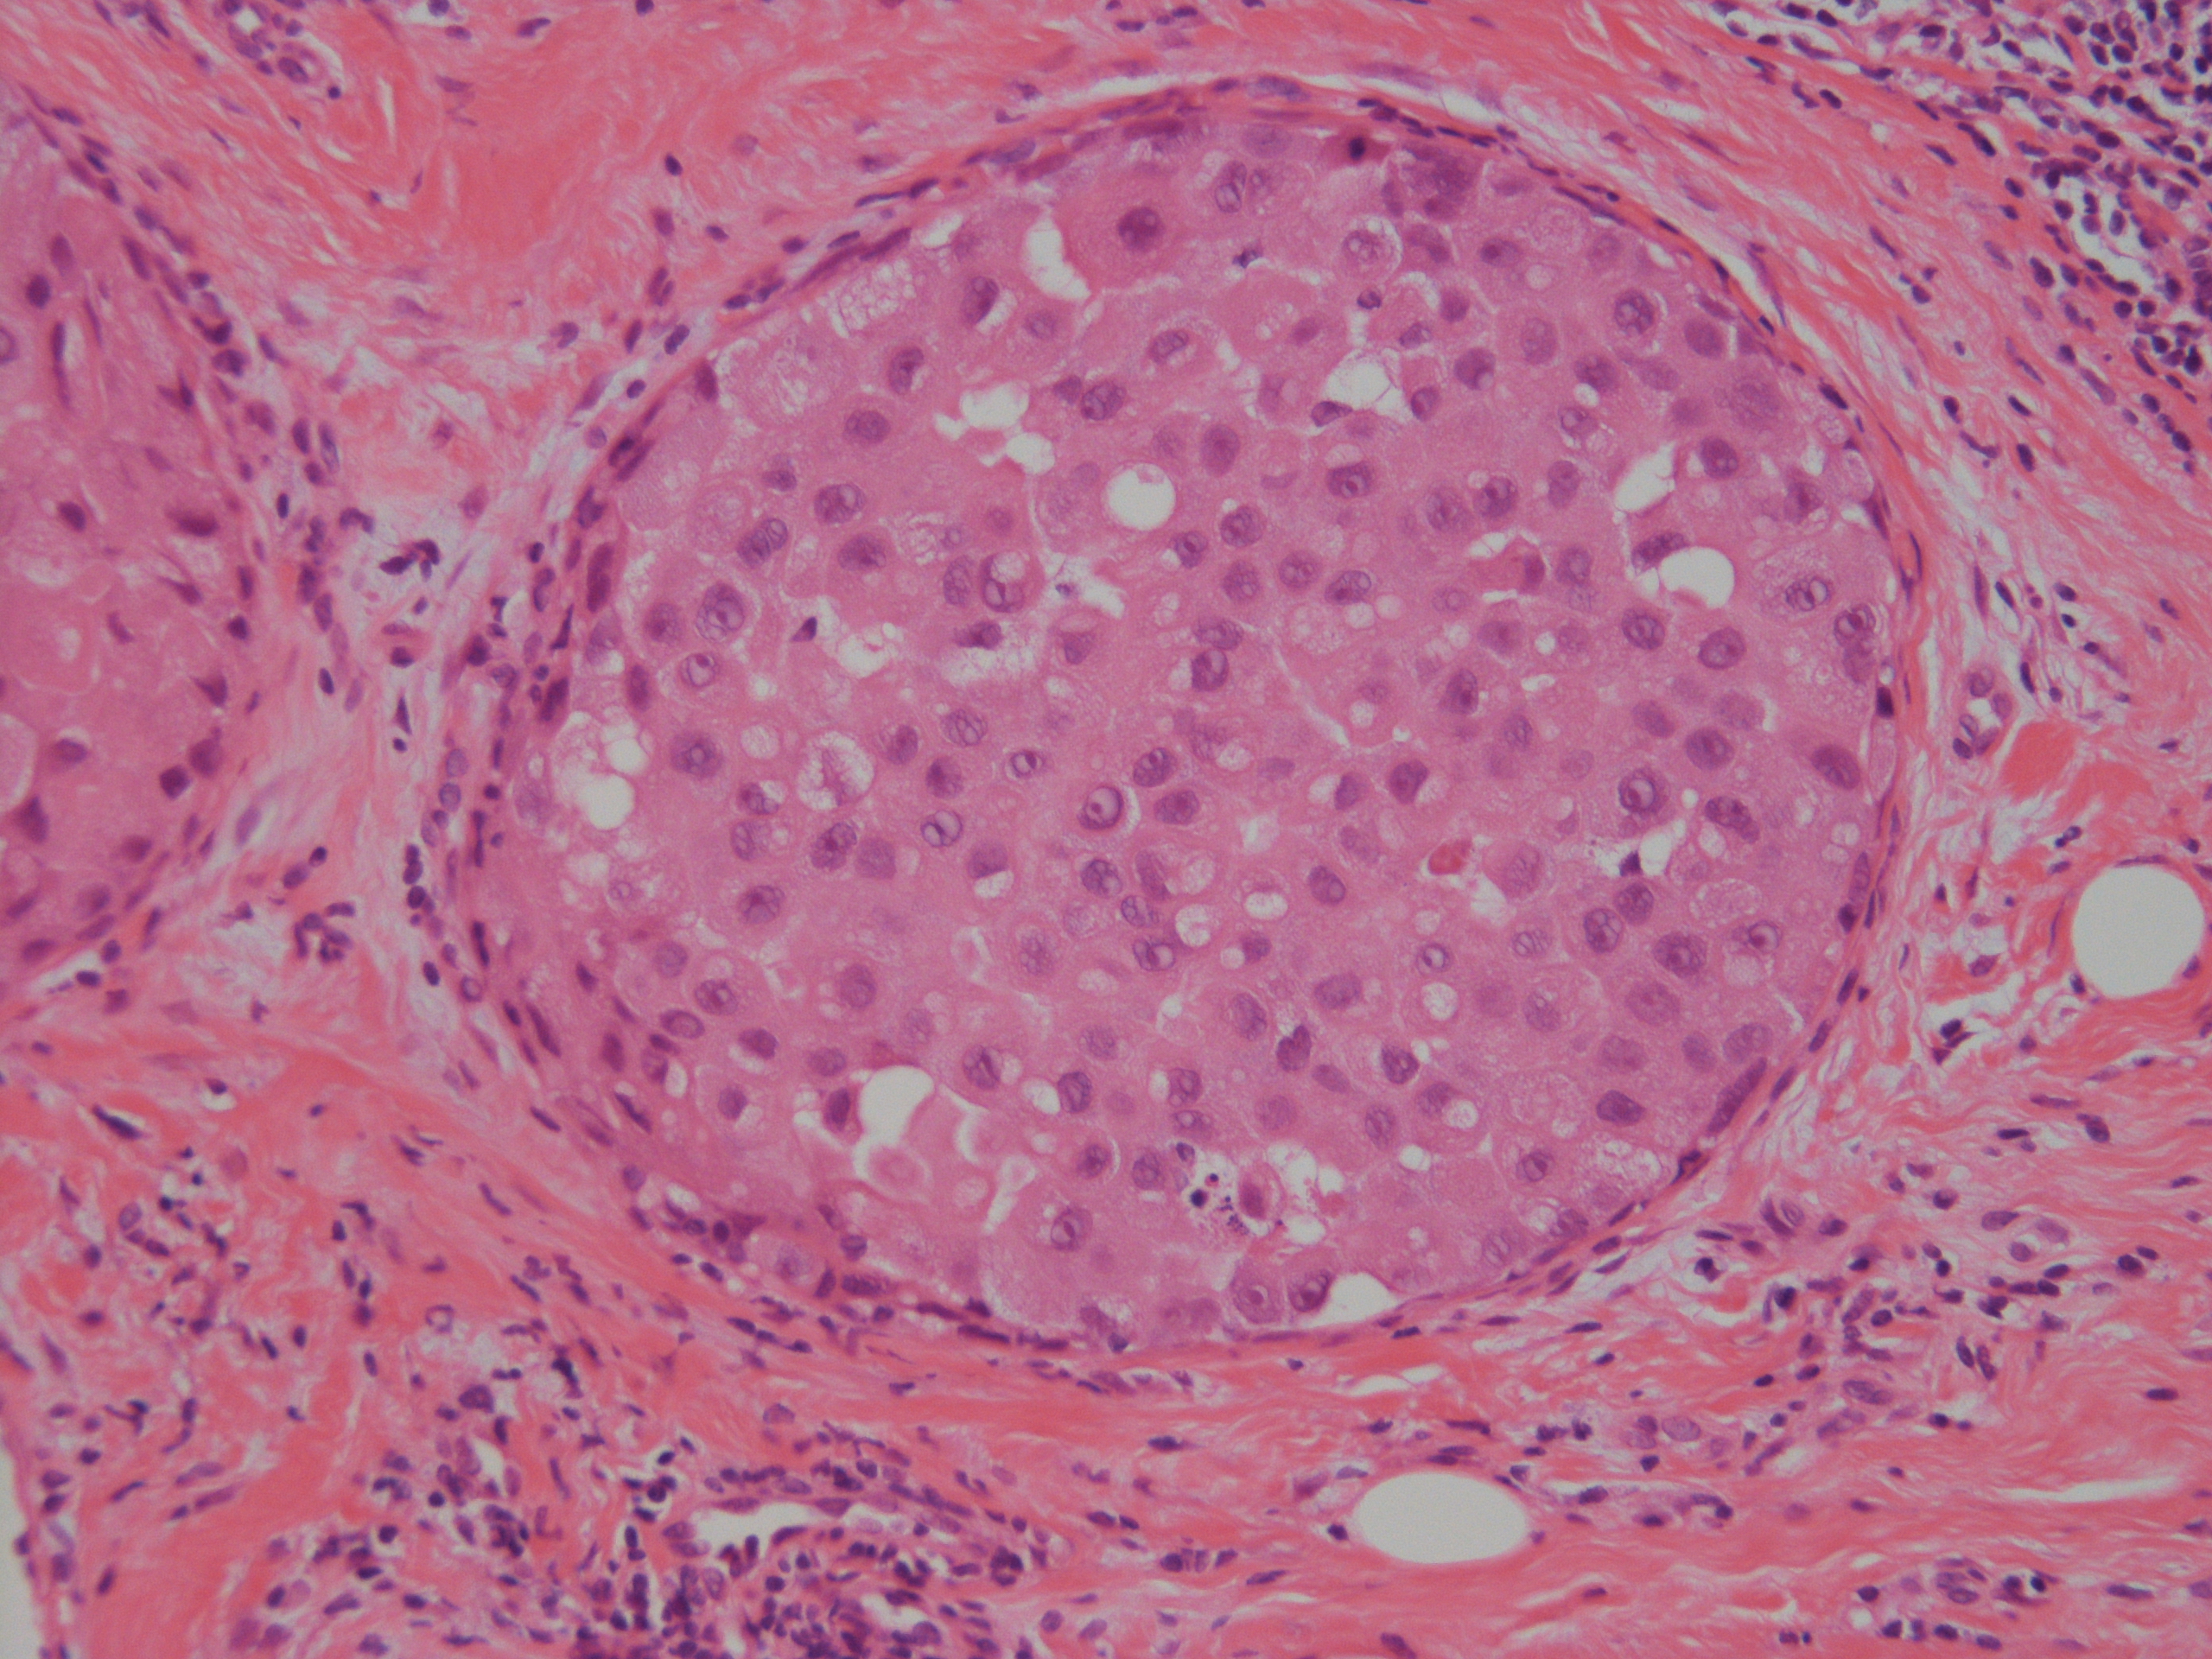

[組織所見]

組織では免疫染色も含め総合的に浸潤部は小葉癌(ER+、 HER2-)であったが、

乳管内癌成分においてもE-cadherinの染色性が減弱しており、非浸潤性乳管癌か非浸潤性小葉癌(多形型)か判断が難しいが、

乳管内癌成分はER-、HER2(3+)で形質発現はクリアカットに分かれ、最終的に非浸潤性乳管癌と診断された。